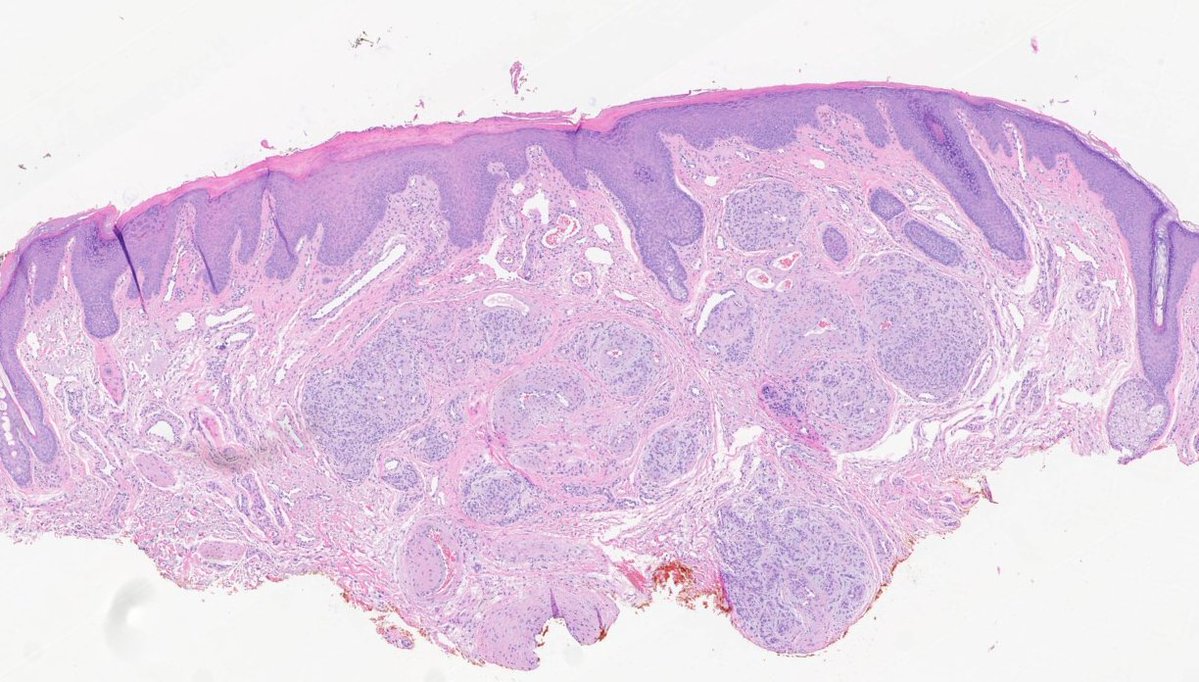

#dermpath 62 yo Man upper back. You worried about this โ€œnevusโ€ ? @david_terrano @et565 @DrGeeONE @SGottesmanMD @kis_lorand @HoustonArsenal @Dr_Jukic @glinglerimek @pembeoltulu @gonzadetoro stains are SOX10 and P16โ€ฆ